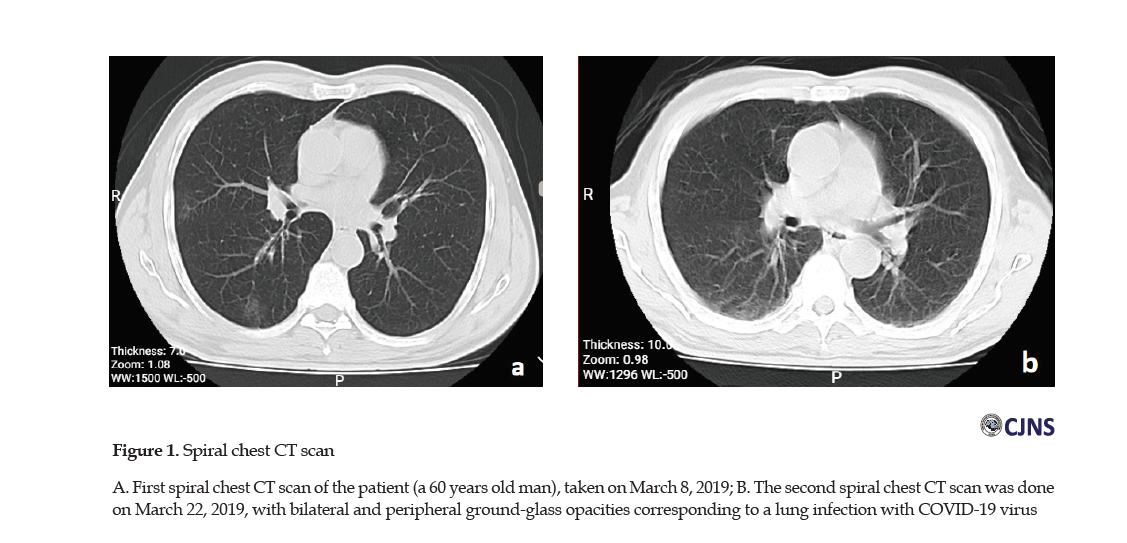

The patient’s drug history included Aspirin, metformin 500 mgBD, valsartan 80 mg/d, amlodipine 2.5 mg/d, and atorvastatin 40 mg/d. During his hospitalization, we started Clexane 60 daily for the prevention of Deep Vein Thrombosis (DVT), and due to the findings of his spiral chest Computerized Tomography (CT) scan (taken on March 8, 2019) corresponding to a lung infection with COVID-19 virus (bilateral and peripheral ground-glass opacities) (Figure 1A).

1. Because about 26 days had passed since the onset symptoms of the disease, an infection specialist was consulted for starting methylprednisolone prescription. The request was not agreed upon due to the findings of the second spiral chest CT scan performed on March 22, 2019 (Figure 1b).

The patient’s spiral chest CT scan at the time of admission was indicative of lung involvement with bilateral and peripheral ground-glass opacities [17]. Although the most apparent abnormalities on chest CT were observable for 10 days, they disappeared 14 days after the onset of symptoms that might last for a longer period [18].